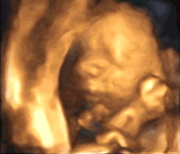

我们引进了技术更为先进的四维彩超设备

相比普通的超声影像(四维彩超)

就像1080p超清画面

更加清晰立体地展示宝宝的模样

而且还是“GIF”动图